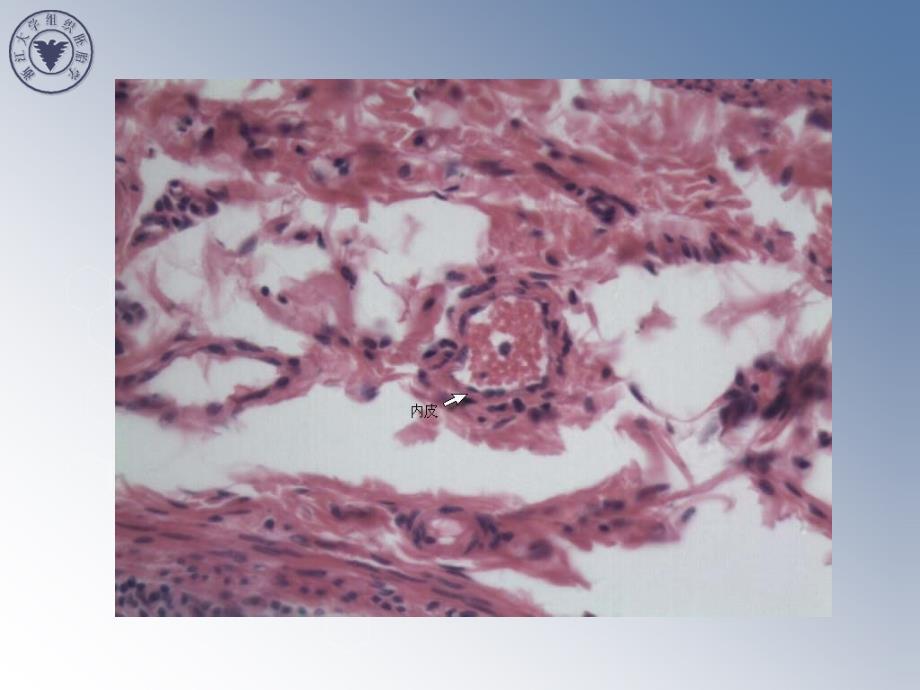

结缔组织结缔组织((Connective tissue))指导教师:李冬梅指导教师:李冬梅 要求切片:1.疏松结缔组织(No.4 铺片 绘图)2.致密结缔组织(No.14 手指皮)3.脂肪组织(No.6 淋巴结) 疏疏疏疏松松松松结结结结缔缔缔缔组组组组织织织织间质间质间质间质纤维:胶原纤维、弹性纤维、网状纤维纤维:胶原纤维、弹性纤维、网状纤维纤维:胶原纤维、弹性纤维、网状纤维纤维:胶原纤维、弹性纤维、网状纤维基质:蛋白多糖、糖蛋白、组织液基质:蛋白多糖、糖蛋白、组织液基质:蛋白多糖、糖蛋白、组织液基质:蛋白多糖、糖蛋白、组织液细胞细胞细胞细胞成纤维细胞成纤维细胞成纤维细胞成纤维细胞固定细胞固定细胞固定细胞固定细胞脂肪细胞脂肪细胞脂肪细胞脂肪细胞未分化间充质细胞未分化间充质细胞未分化间充质细胞未分化间充质细胞巨噬细胞巨噬细胞巨噬细胞巨噬细胞游走细胞游走细胞游走细胞游走细胞浆细胞浆细胞浆细胞浆细胞肥大细胞肥大细胞肥大细胞肥大细胞白细胞白细胞白细胞白细胞疏松结缔组织疏松结缔组织疏松结缔组织疏松结缔组织((((loose connective tissueloose connective tissue)))) LCT:HE X400Collagenous fiber, Elastic fiberFibroblast, Macrophage1.疏松结缔组织(No.4 铺片 绘图) Small intestine:LCT HE X40 Submucosa of small intestine: LCT HE X400 In the section , epidermis is violent stained. Under epidermis,the dermis is pink and compose of denes connective tissue. epidermis dermis 2.致密结缔组织致密结缔组织(No.14 手指皮手指皮) Skin :DCT HE X40 Skin: DCT HE X400 3.脂肪组织脂肪组织(No.6 淋巴结淋巴结) Lymph node: Adipose tissue HE X400 Lymph node: Reticular tissue HE X400示示 教教 Lymph node: Reticular tissue Silver X100 Lymph node: Reticular tissue Silver X400 Mast cells The drawingLoose connective tissue H&E stain 400×MacrophageCollagenous fiberElastic fibersFibroblast 。